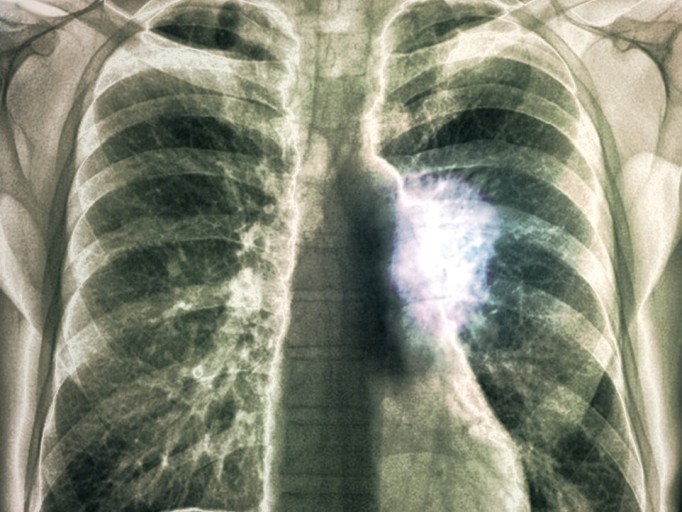

- 정기적인 건강 검진: 특히 흡연자나 가족력이 있는 경우, 저선량 흉부 CT와 같은 정밀 검진을 통해 조기에 발견해야 합니다.